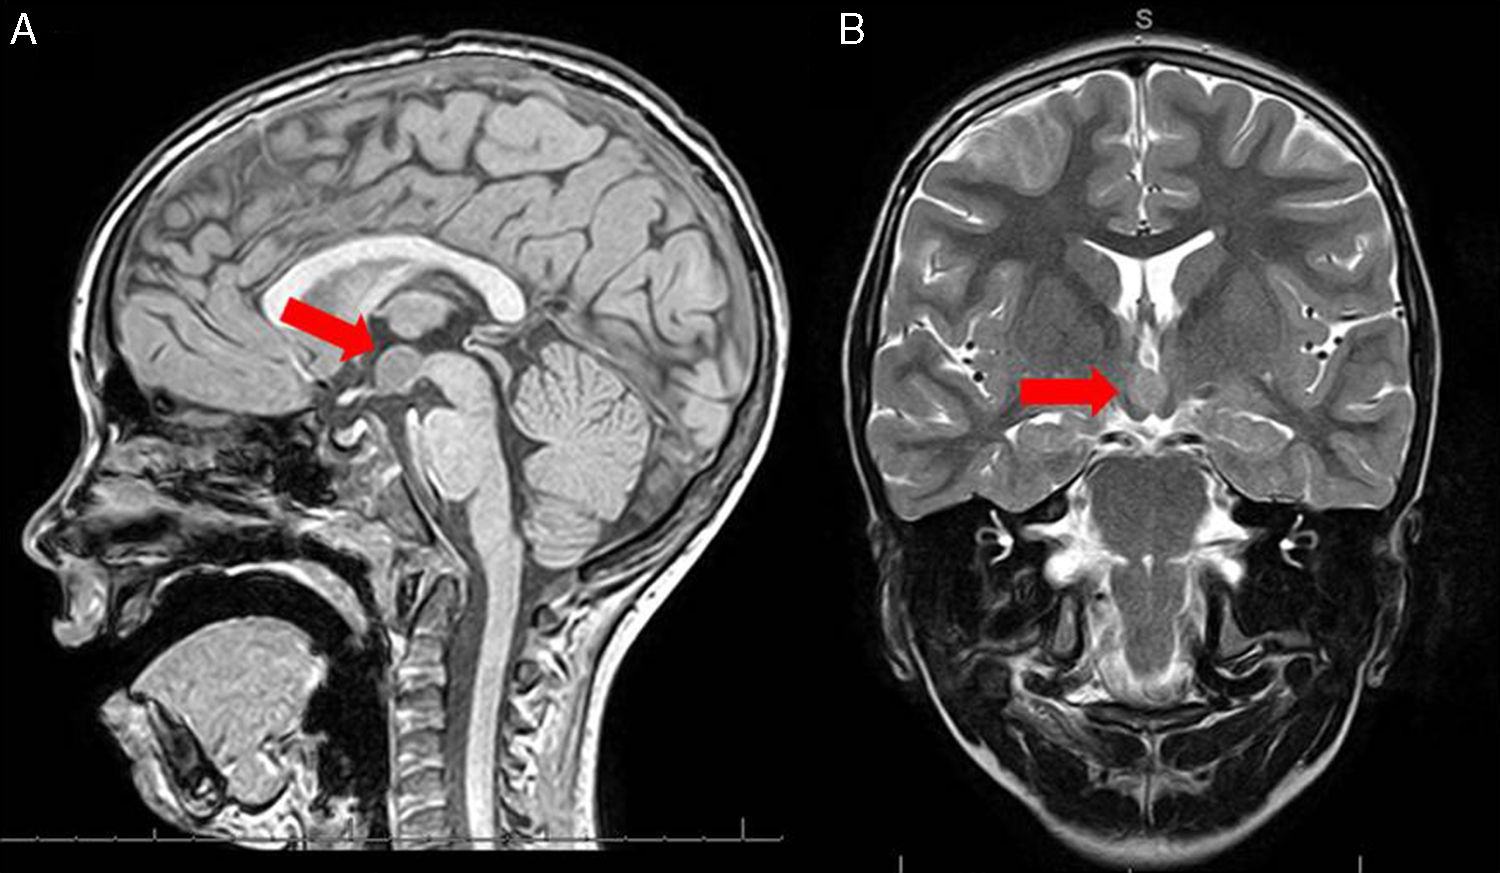

L'ipofisi o ghiandola pituitaria è una ghiandola endocrina situata alla base del cranio, nella sella turcica dell'osso sfenoide.

A causa della vicinanza al nervo ottico, può verificarsi una perdita del campo visivo se il tumore è molto grande. In questo caso, un intervento è strettamente necessario.